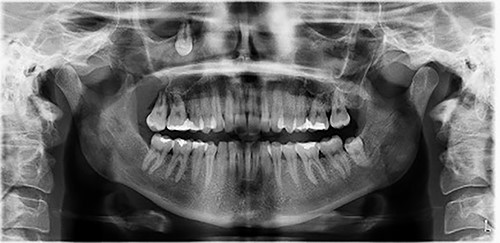

A 29-year-old female patient was referred from the Maxillofacial surgeons to ENT outpatients, for assessment of a loose upper right molar and right-sided retro-orbital pain, ongoing for 4 months. She had no past medical or surgical history and was a lifelong non-smoker with no significant family history. Imaging with a orthopantomogram (Fig. 1) depicted an ectopic tooth in the right maxillary sinus. CT imaging further characterized a thin-walled cystic mass in the right maxillary sinus (Figs 2 and 3), and opacification of the maxillary and ethmoidal air cells is also visualized alongside the afore mentioned ectopic tooth.

Orthopantomogram depicting the ectopic tooth in the right maxillary sinus.